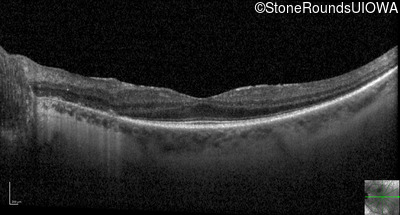

Optical Coherence Tomography - Left - 20/32 -1

Exemplar / OCT Stack